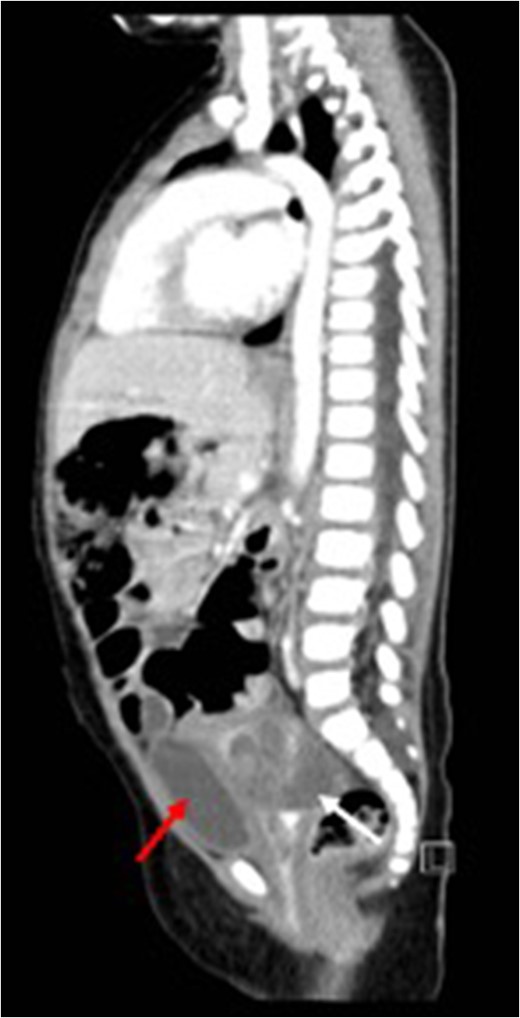

Before treatment sagittal view (CT) showing a large mass (white arrow) compressing on bladder (red arrow).

Sagittal view (CT) for the mass (white arrow) post-chemotherapy showing reduction in size (red arrow) bladder.

Post-treatment sagittal view (CT) with no evidence of recurrence arising from the uterus (red arrow) bladder.